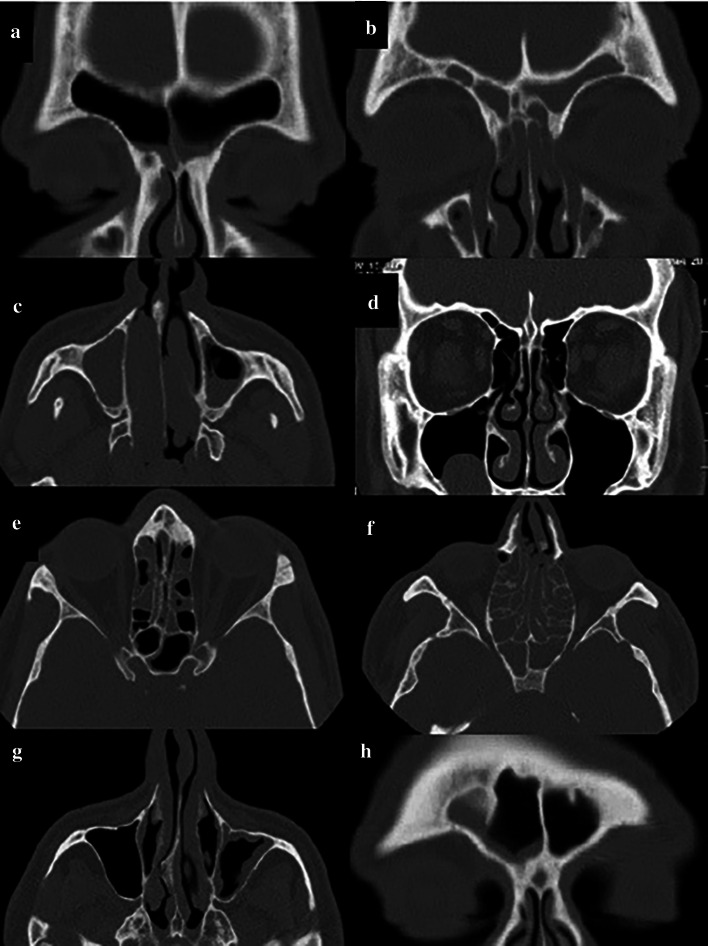

According to the Lund-Mackay scoring system and using the coronal and axial sections, each sinus (frontal, anterior ethmoid, posterior ethmoid, maxillary, and sphenoid) was allocated a score from 0 to 2 (0: no abnormality, 1: partial opacification, 2: complete opacification). Also, the OMC was allocated a score of 0 (not obstructed) or 2 (obstructed). According to this scoring system, each side with a score ≥ 6 with maxillary sinus involvement was assigned to the maxillary sinusitis group while the sides with a score < 3 and absence of maxillary sinusitis were assigned to the healthy control group without maxillary sinusitis (Fig. 1).

Fig. 1.

Scoring of CT scans according to the Lund-Mackay scoring system. a Coronal section of the right and left frontal sinus with score 1; b Coronal section of the right and left frontal sinus with score 2; c Axial section of the right maxillary sinus with score 2 and left maxillary sinus with score 1, d Coronal section of the left OMC with score 2 and right OMC with score 0; e Axial section of the anterior and posterior ethmoid and sphenoid sinuses of each side with score 1; f Axial section of the anterior and posterior ethmoid and sphenoid sinuses of each side with score 2; g Axial section of the maxillary sinus of the right side with score 0 and left side with score 1; h Coronal section of the frontal sinus with score 1 in the right side and score 0 in the left side